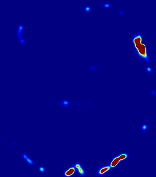

LesionRefer to captionRefer to captionRefer to captionRefer to captionRefer to captionRefer to caption𝐕rgbsubscript𝐕𝑟𝑔𝑏{\bf{V}}_{rgb}Refer to captionRefer to captionRefer to captionRefer to captionRefer to captionRefer to caption𝐕2subscriptnorm𝐕2{\|\bf{V}}\|_{2}Refer to captionRefer to captionRefer to captionRefer to captionRefer to captionRefer to captionRefer to caption3.53.53.52.82.82.82.12.12.11.41.41.40.70.70.70.00.00.0(mm/s)𝑚𝑚𝑠(mm/s)D𝐷DRefer to captionRefer to captionRefer to captionRefer to captionRefer to captionRefer to captionRefer to caption0.0200.0200.0200.0160.0160.0160.0120.0120.0120.0080.0080.0080.0040.0040.0040.0000.0000.000(mm2/s)𝑚superscript𝑚2𝑠(mm^{2}/s)Slice #1Slice #2Slice #3Slice #4Slice #5Slice #6

Figure 4: PIANO feature maps for another patient in the ISLES 2017 training set, where the lesion is located in the right hemisphere. Top row: segmented stroke lesion region (white) on different slices. The corresponding slices for the PIANO feature maps are shown in the following rows.

For a better insight into an estimated velocity field 𝐕𝐕{\bf{V}} and diffusion field 𝐃𝐃{\bf{D}}, we compute the following maps: (1) 𝐕rgbsubscript𝐕𝑟𝑔𝑏{\bf{V}}_{rgb}: Color-coded orientation map of 𝐕=(Vx,Vy,Vz)T𝐕superscriptsuperscript𝑉𝑥superscript𝑉𝑦superscript𝑉𝑧𝑇{\bf{V}}=(V^{x},V^{y},V^{z})^{T}, obtained by normalizing 𝐕𝐕{\bf{V}} to unit length and mapping its 3 components to red, green, blue respectively; (2) 𝐕2subscriptnorm𝐕2\|{\bf{V}}\|_{2}: 222 norm of 𝐕𝐕{\bf{V}}; (3) D𝐷D: scalar field in Eq. 5.

Fig. 3 and Fig. 4 show the PIANO feature maps estimated from two ISLES 2017 patients: all are highly consistent with the lesion in both cases. Details of the blood flow trajectories are revealed in 𝐕rgbsubscript𝐕𝑟𝑔𝑏{\bf{V}}_{rgb} by the ridged patterns and the sharp changes of colors in the unaffected (right) hemisphere, while the flat patterns appearing within the lesion provide little directional information about the velocity and indicate low velocity magnitudes. Velocity magnitudes are more directly visualized via 𝐕2subscriptnorm𝐕2\|{\bf{V}}\|_{2}, from which one can easily locate the lesion where 𝐕2subscriptnorm𝐕2\|{\bf{V}}\|_{2} is low. D𝐷D also indicates lower diffusion values in the lesion, though with less contrast potentially due to the fact that it captures the accumulated effect of CA diffusion at the voxel-level.